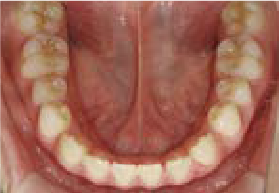

これから生えてくる永久歯のスペースがなく、歯が並ぶ余地がほとんどありませんでした。

さらに、上からあごの骨を見たところ、中央がくびれた“ひょうたん型”に変形しており、あごの成長にも偏りが見られました。

診断の結果、前歯の中心も少し左にずれており、特に犬歯が生えるスペースが足りない状態でした。

飲み込むときに下くちびるに力が入り、顔の左側にゆがみが出ている様子も確認できました。

治療を終えて

犬歯が歯ぐきの中に埋まっていたため、透明のマウスピース型装置で生えるスペースを作り正しい位置に導きました。もちろん抜歯せずに歯並びを整えることができました。お口の中がとても小さく、型どりの際にオエッとなる反応が強く、当時は装置を作るのが大変でした。しかし現在では3Dスキャナーと3Dプリンターを活用しスムーズに治療できます。

主訴・治療内容 「あごが小さいから、歯がきれいに並ばない」と他院で言われ永久歯を抜く矯正をすすめられていました。

本当に非抜歯で治療できるのか心配されていましたが、治療方法を丁寧にご説明し、お任せいただきました。

治療期間 5年

費用 550,000円(税込)